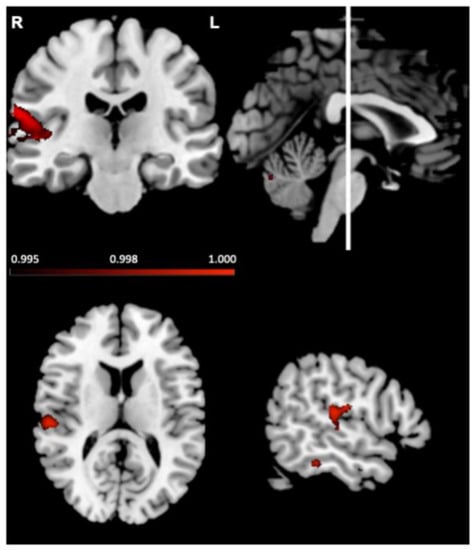

| Regions | Hemisphere | MNI Coordinates | Number of Voxels | ||

|---|---|---|---|---|---|

| x | y | z | |||

| Planum temporale; supramarginal gyrus; precentral gyrus; superior temporal gyrus; Heschl’s gyrus (H1 and H2) | right | 62 | −22 | 18 | 463 |